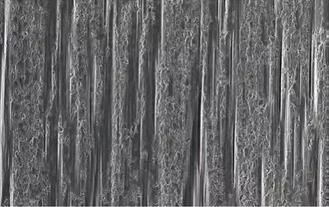

PMMA 基樹脂通過甲基丙烯酸甲酯(MMA)的自由基聚合而形成。在聚合過程中所產(chǎn)生的聚合物鏈的長度及其網(wǎng)狀連接直接與壓力、溫度分布和聚合的持續(xù)時間相關(guān)。這些參數(shù)對聚合材料的機械和化學(xué)性能有很大的影響。PMMA基樹脂從100℃ 起可塑性變形。此外,它們可溶于自己的單體,因此可以促成一個良好的結(jié)合而進一步產(chǎn)生其他的PMMA樹脂。如今的PMMA基樹脂在透光性上已經(jīng)在某些方面優(yōu)于陶瓷,并因此在患者口內(nèi)顯現(xiàn)出了極高的美觀效果(圖2)。但它們也存在一個很大的缺點,就是彈性模量非常低,范圍在2.7至3.2GPa之間,因此即使在低負載下也會導(dǎo)致塑性變形。在掃描電子顯微鏡(SEM Scanning electron microscope)圖像中可以清楚地識別出無填料的矩陣結(jié)構(gòu)(圖3)。

圖3:在人為模擬咀嚼后,由無填料PMMA 制作的修復(fù)體冠的SEM圖像(圖片來源:Max Hummel博士)。